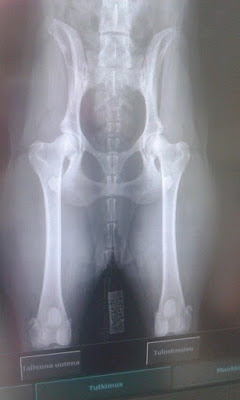

Ditan (Traxa's Falling For You) lonkat A/A ja kyynärät 0/0! JES!

Tässä vielä kännykkäversiot luustokuvista: